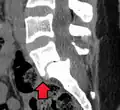

MRI of L5-S1 anterolisthesis- X-ray of a grade 4 anterolisthesis at L5-S1 with spinal misalignment indicated

Anterolisthesis L5/S1

Anterolisthesis L5/S1. Blue arrow normal pars interarticularis. Red arrow is a break in pars interarticularis.